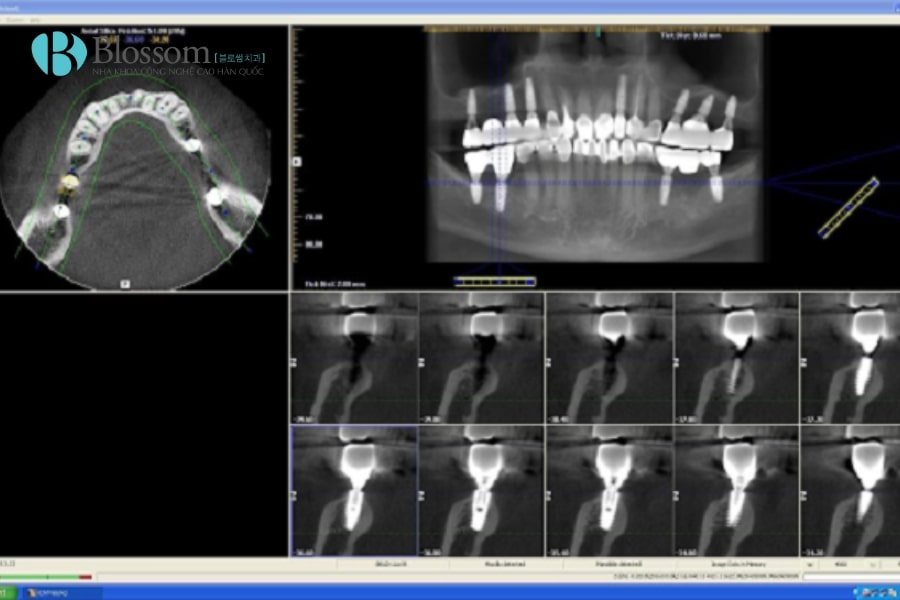

CT Cone Beam giúp đánh giá chính xác chất lượng và khối lượng xương hàm, vị trí dây thần kinh và mạch máu, từ đó lập kế hoạch cấy ghép Implant an toàn. Hình ảnh 3D cho phép chọn đường kính Implant phù hợp, dự đoán có cần ghép xương và tránh chèn ép các cấu trúc quan trọng như xoang hàm trên hay dây thần kinh hàm dưới, đảm bảo tuổi thọ lâu dài của trụ Implant.

- Lập kế hoạch điều trị chính xác: Hình ảnh 3D toàn diện giúp bác sĩ đánh giá mật độ xương, vị trí răng, đường đi dây thần kinh, từ đó lên kế hoạch cấy ghép Implant, chỉnh nha hoặc nhổ răng khôn an toàn.

- Ứng dụng đa dạng trong nha khoa: Hỗ trợ cấy ghép Implant, chỉnh nha, nhổ răng khôn, điều trị nội nha và chẩn đoán bệnh lý hàm mặt, đồng thời nâng cao hiệu quả thẩm mỹ và chức năng sau điều trị.